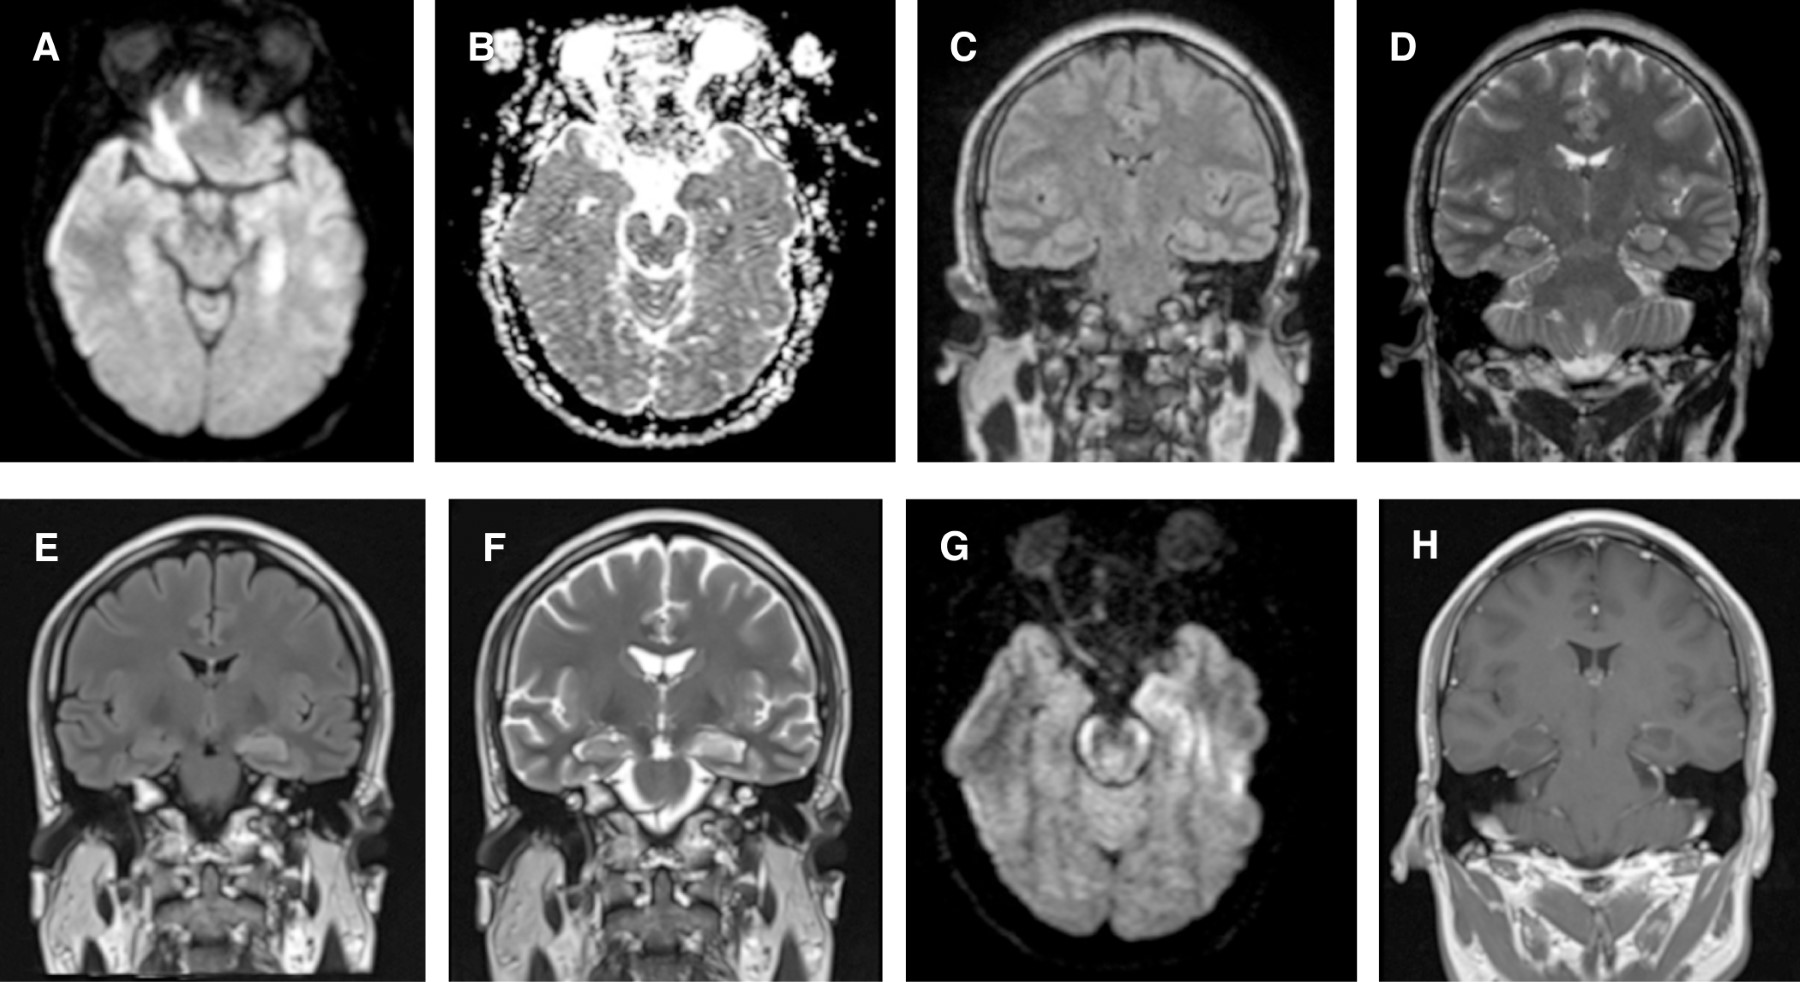

Los estudios de laboratorio mostraron acidosis metabólica (pH 6.92, HCO3 8.4 lactato 22), marcadores inflamatorios elevados (leucocitosis 19,600, proteína C reactiva 12.4, procalcitonina 2.23), elevación de transaminasas (ALT 150, AST 95.4, GGT 269), disfunción renal (creatinina 5.72, BUN 41) y rabdomiólisis (CK 3445, CK-MB 50.7, troponina 11, mioglobina 762). La RM cerebral mostró restricción a la difusión en hipocampo izquierdo y corteza del giro parahipocampal homolateral que se corroboró en ADC (Figura 1A-D). De la punción lumbar se obtuvo líquido de aspecto turbio, con presión de apertura de 300 cmH2O, citoquímico con pleocitosis linfocitaria (células 189, 96% mononucleares), proteínas 21 mg/dL, glucosa 91 mg/dL). El electroencefalograma digital mostró actividad theta generalizada entremezclada con actividad rápida por efecto farmacológico (diazepam), ondas agudas en región temporal anterior izquierda, actividad delta de gran amplitud en regiones frontales, rítmica e intermitente (FIRDAS), y frecuentes ondas lentas de morfología angulada periódicas generalizadas con ocasional lateralización hacia ambas regiones temporales (Figura 2A y B). Por la sospecha de encefalitis infecciosa se inició cobertura empírica con ceftriaxona, vancomicina, ampicilina, aciclovir y dexametasona.

Debido al desarrollo de IA y de movimientos anormales se consideró la posibilidad de una encefalitis autoinmune, por lo que se determinaron anticuerpos antirreceptor de NMDA, anticuerpos intraneuronales (anti-Hu, anti-Yo, anti-Ri, antiamfifisina, anti-CRMP5) y bandas oligoclonales en LCR, los cuales fueron negativos. No se exploraron otros anticuerpos contra antígenos de superficie y proteínas sinápticas (antirreceptor AMPA, antirreceptor GABAB, antirreceptor LGI1, antirreceptor CASPR-2). El estudio microbiológico del LCR fue negativo para bacterias, hongos, micobacterias y para los virus herpes tipo 1 (HSV 1), herpes tipo 2 (HSV 2), varicela zóster (VZV), citomegalovirus, Epstein-Barr virus, Coxsackie A, Coxsackie B, Echovirus y virus West Nile (VWN). La serología para VIH y el VDRL sérico fueron negativos. Otros estudios para investigar enfermedades sistémicas fueron negativos (perfil tiroideo, anticuerpos antinucleares, anticardiolipinas, marcadores tumorales). La punción lumbar de control, realizada el sexto día de tratamiento antimicrobiano, mostró disminución de la pleocitosis (células 50, mononucleares 100%, proteínas 22.4 mg/dL, glucosa 66 mg/dL). La RM cerebral de control, con dos semanas de diferencia de la primera, demostró persistencia de la hiperintensidad en cuerpo y cola del hipocampo izquierdo en T2/FLAIR y de la restricción a la difusión en la misma zona, pero sin reforzamiento tras la administración de gadolinio (Figura 1E-H).

Figura 1